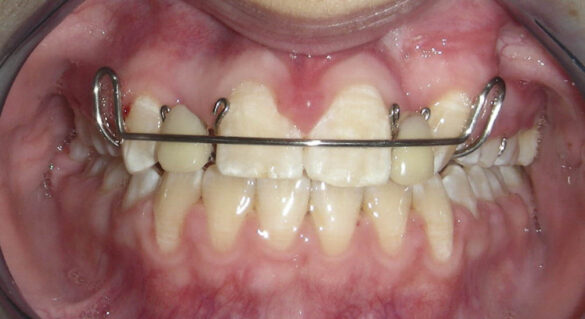

A doua etapă a tratamentului a fost amânată până în aprilie 2006, când pacienta a împlinit vârsta de 11 ani şi 5 luni. În acel moment, fetiţa prezenta erupţie şi dezvoltare radiculară adecvată, astfel că aparatele fixe aplicate acum n-ar fi purtate o perioadă îndelungată. Ocluzia inversă frontală şi angrenajul invers lateral fuseseră corectate; totuşi, exista o diastemă mare, în principal cauzată de lipsa incisivilor laterali superiori (fig.3). În acest moment, radiografia panoramică relevă anodonţia incisivilor laterali maxilari şi a premolarului secund drept mandibular, o anatomie redusă a rădăcinilor incisivilor centrali superiori, incluzia caninului superior stâng şi dezvoltarea întârziată a rădăcinii celui de-al doilea premolar inferior (fig. 4).

În aprilie 2009, după 37 luni de tratament, au fost îndepărtate aparatele fixe (fig. 6). Pentru contenţie, s-a aplicat un retainer fix colat pe faţa linguală a celor şase dinţi frontali inferiori şi o placă palatinală Hawley care încorporează dinţi acrilici în dreptul incisivilor laterali pentru a menţine un aspect estetic până când medicul protetician va putea realiza punţile dentare. În plus, s-a utilizat un arc vestibular care să consolideze contenţia şi care să permită aplicarea unor forţe uşoare, cu direcţie linguală, dacă este necesar.25 Croşetele ”în deget” sunt situate distal de incisivii centrali maxilari şi mezial de caninii superiori, pentru a permite o deplasare discretă mezio-distală a dinţilor, dacă este necesar (fig. 7).Înainte de îndepărtarea aparatului, a fost consultat medicul protetician. S-a pus problema dacă pacienta ar avea dificultatea de a purta pe termen lung un aparat mobil de contenţie, din cauza dificultăţilor de respiraţie şi a tusei, asociate cu fibroza chistică. În plus, din cauza anodonţiei de incisivi laterali superiori, osul alveolar este dezvoltat insuficient şi prezintă, astfel, dimensiuni prea reduse pentru inserarea implantelor dentare; procedura de augmentare a ţesuturilor moi şi dure ale crestei alveolare ar fi inevitabilă. Vârsta pacientei şi creşterea şi dezvoltarea corespunzătoare au fost, de asemenea, luate în considerare.19 Ortopantomograma finală relevă anodonţia molarilor de minte inferiori şi a celui superior drept pe lângă anodonţia incisivilor laterali maxilari şi a premolarului secund drept inferior. De asemenea, se remarcă aplatizarea rădăcinilor incisivilor centrali maxilari, care era prezentă şi pe radiografia efectuată înainte de tratament (fig.8).